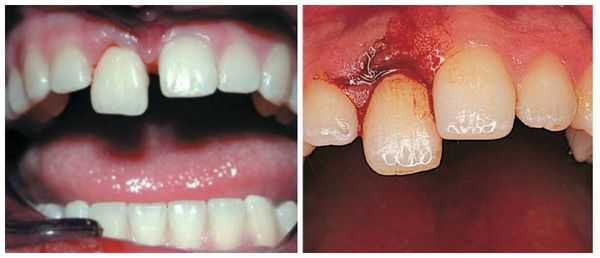

(Слева) На фотографии определяется вколачивание центрального и бокового резцов верхней челюсти справа. Обратите внимание на кровотечение из трещины в десне - признак острой травмы.

(Справа) На периапикальной рентгенограмме у этого же пациента определяется перелом резцового края. (Слева) На фотографии у этого же пациента определяется постепенное самопроизвольное выдвижение зуба и заживление периодонта.

(Справа) На периапикальной рентгенограмме у этого же пациента определяется рарефицирующий остеит возле вершины корня центрального резца верхней челюсти. Рекомендуется лечение корневою канала. Обратите внимание, что гибель пульпы произошла до закрытия вершины корня зуба; вершина корня открыта. (Слева) На фотографии у этого же пациента определяется полное спонтанное выдвижение вколоченною зуба. Сломанные резцовые края могут быть восстановлены композитным материалом.

(Справа) На периапикальной рентгенограмме у этою же пациента - состояние после лечения пульповых каналов с обтурацией их гуттаперчей. Обратите внимание на наружную резорбцию корней обоих резцов.